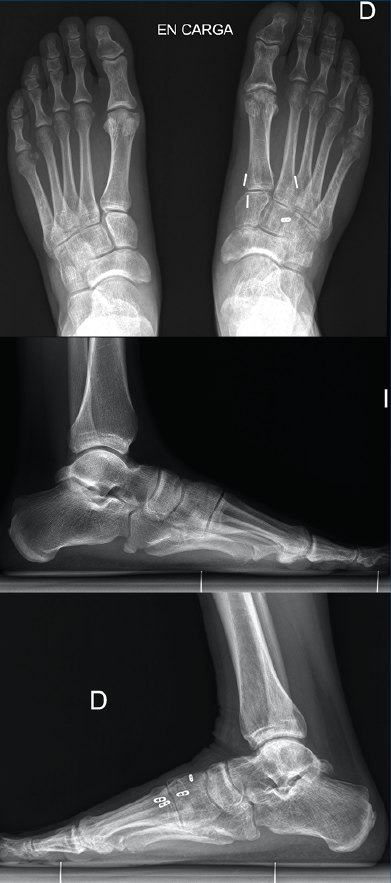

Figura 1. Caso 1. A: radiografía anteroposterior (AP) sin carga; B: radiografía oblicua sin carga; C: radiografía AP con carga con diástasis en la articulación de Lisfranc; D: radiografía lateral con carga.

Se trata de un varón de 32 años diagnosticado de lesión sutil de Lisfranc en urgencias tras un traumatismo deportivo sin especificar el mecanismo. Se realiza estudio radiográfico y tomográfico objetivando diástasis de 2 mm articular en el pie derecho sin lesión ósea (Figuras 1A y 1B). Se decide realizar tratamiento conservador con férula y descarga. Se hace una revisión a las 2 semanas, manteniendo la diástasis previa, pero en la revisión a las 6 semanas se confirma diástasis de 5 mm en la radiografía en carga, por lo que se indica tratamiento quirúrgico (Figuras 1C y 1D).